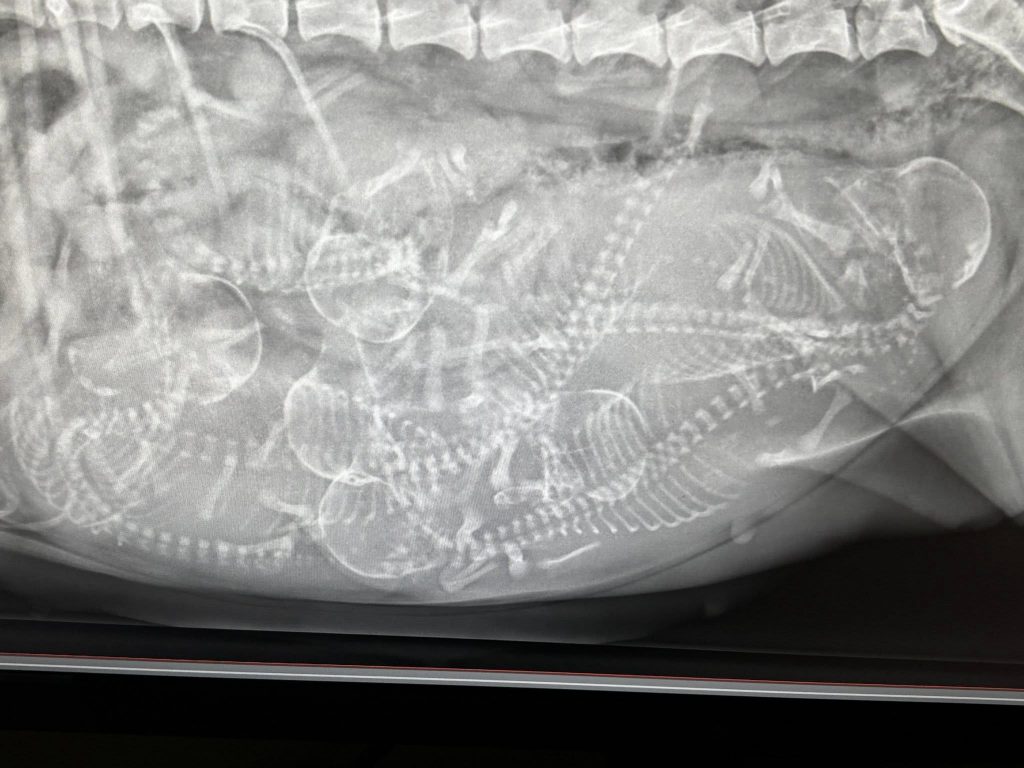

Maijan kanssa käytiin tiineys rtg- ja suureksi yllätyksekseni, ei niin valtavan Maijan mahassa muhii peräti kuuden! (6) pikku mittelspitzin lauma!

Painoa oli 56 vrk kohdalla 9,4 kiloa, eli kyllähän Maija on tukevasti tiineenä, siitä ei ole epäilystäkään.